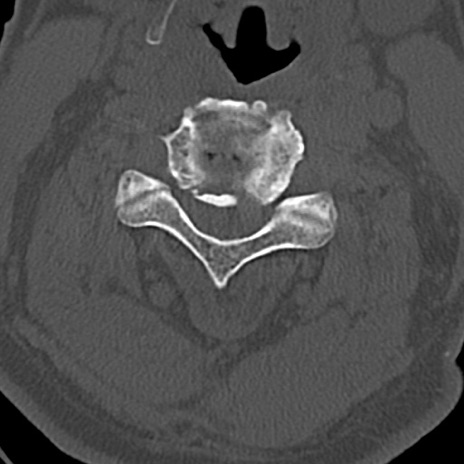

頚椎CT

横断像